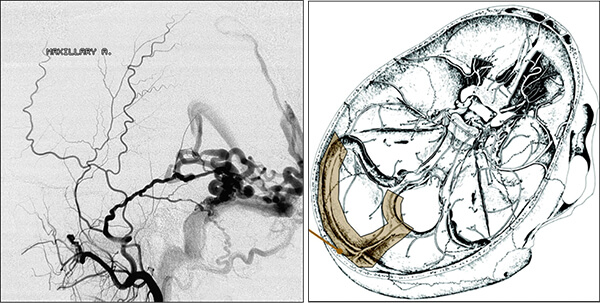

Η αξονική αγγειογραφία έχει ελαττωμένη ευαισθησία έναντι της μαγνητικής αγγειογραφίας.

Παρ´ όλα αυτά η συμβατική ενδαρτηριακή αγγειογραφία είναι η πιό ακριβής γιά την αναγνώριση αλλά και την κατηγοριοποίηση των ΑΦΔ της σκληράς μήνιγγας.

Η αρτηριακή προσπέλαση:

- Η χρήση μικροσωματιδίων δεν είναι αποτελεσματική επειδή η επανασηραγγοποίηση και η υποτροπή των συμπτωμάτων είναι σχεδόν πάντα ο κανόνας.

- Η χρησιμοποίηση κυανο-ακρυλικής κόλλας σαν μόνιμο αποφρακτικό υλικό είναι αναγκαίο.

- Από την άλλη πλευρά το Onyx πλεονεκτεί καθώς κατά την έγχυση από ένα μόνο κατάλληλο μηνιγγικό κλάδο μπορούμε να εξαλείψουμε όλη την επικοινωνία, με μεγάλο ποσοστο επιτυχίας.